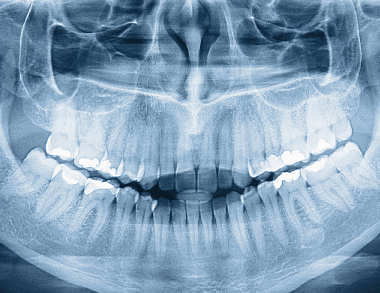

Dental X-rays are essential diagnostic images that use low levels of radiation to capture detailed pictures of your teeth, roots, and jawbone. They reveal hidden structures and problems not visible during a regular oral exam.

Common types include bitewing X-rays to check for cavities between teeth, periapical to view the entire tooth root, and panoramic images for a broad overview of the jaws, teeth, and joints.